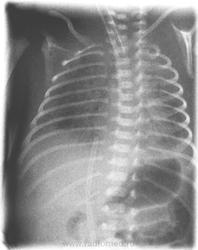

Новорождённый, недоношенный.Первые часы после рождения. Снимок выполнен, как стадартное исследование у недоношенных. Что мы видим и как можно оценивать картину?

Написал бы диффузное снижение пневматизации легочных плей, расценил бы как рентгенпризнаки  пневмопатии.

А, респираторный дистресс-синдром новорождёных ( синоним синдром гиалиновых мембран)? Не тянет?

Отчего же, тянет. Просто, на мой взгляд, это больше клиническое понятие, чем рентгеновское.

Понижение прозрачности есть, но на пневмонию не тянет. Если нет клиники и ребенок недоношенный - то всё в пределах нормы.

Разумеется это не норма. Сама бы написала РДСН, но пневмопатия- звучит привлекательнее

Недоношенный ребенок-это уже не норма,поэтому,это понятие условно.Такая картина нормальна даже для доношенного ребенка,почему Вам кажется,что снижена пневматизация?Если бы сделали снимок в нормальном режиме,то легочный рисунок выглядел бы нормальным,а если бы в "мягком"режиме-то вообще бы показался бы усиленным или обогащенным.Здесь имеет место"жесткий" снимок,поэтому возникают проблемы с его интерпретацией

Вы думаете, что это норма. Будем считать, что мнения разошлись. Вообще,  это цифровой отредавктировнный снимок и его можно сделать сколько угодно "жёстким". У этого пациента были выраженные проявления синдрома дыхательных расстройств, он был переведён на аппарат ИВЛ. Думаю здорового ребёнка, с нормой по лёгким на ИВЛ некто бы не перевёл.

Согласна с Вами,что признаки СДР были,раз ребенок на ИВЛ,но рентгенологически-нет.Отцифровать можно любой снимок,но всегда видно в каком режиме он изначально был сделан

ИМХО: синдром лёгочной диссеминации, более выраженный справа.На фоне тени сердца чётко прослеживаются полоски бронхов( на фоне пневматизированной лёгочной ткани, мы бы этого не увидили).Нечёткость контуров средостения и купола диафрагмы слева. Ну, какая же это норма-это патология.

Полоски воздушных бронхов у детей видны практически всегда,"нечеткость" связана с тем,что такой малыш просто не может задержать дыхание во время съемки по команде лаборанта+тахипное=все-таки-норма.Я высказались как и небольшой специалист по детским снимкам.С уважением,Миргалина.

Забыла добавить еще,что ребенок развернут,поэтому кажется разная прозрачность легочных полей слева и справа.О какой диссеминации идет речь?